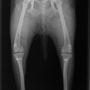

■ 症例24 キャバリア 7か月

左右膝蓋骨内方脱臼(左:グレードⅣ 右:グレードⅢ)

以前から左右後肢の跛行が認められ、整形外科学的検査・レントゲン検査により左右の膝蓋骨脱臼が認められた。症状が重度である左膝の膝蓋骨脱臼整復術を行った。外科手技は縫工筋及び内側広筋の解放、脛骨粗面の外側転位、滑車ブロック形造溝術、内外側関節方の縫縮を実施した。術後一か月時点で、左の膝蓋骨は安定しており経過は良好である。

本症例は成長期における重度の膝蓋骨脱臼であり、術後の再発の可能性もあるため、経過をしっかりと観察していく必要がある。また、今回手術を実施していない右膝に関しても経過を観察し、手術を検討していくこととする。